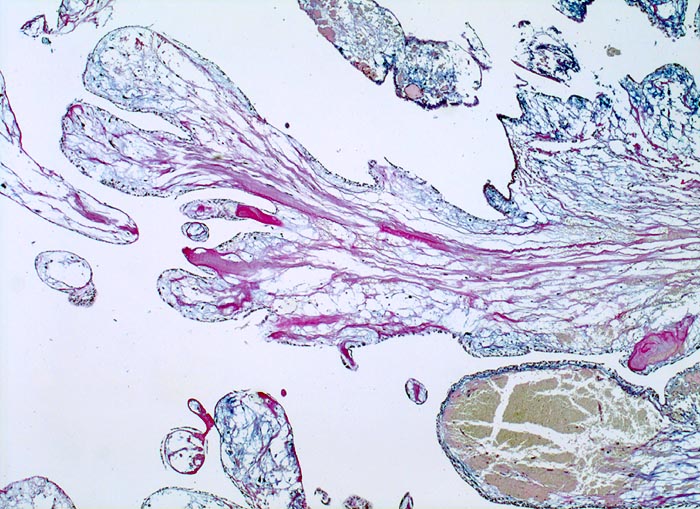

AP/ Vorhofmyxom

Vorhofmyxom